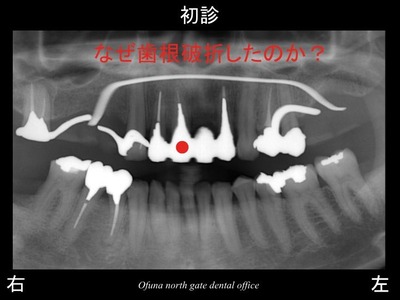

以下は初診時です。

上顎右側の前歯が腫れるとのことで来院されました。

この歯は、歯の根が折れていることが分かりました。

歯根破折 という状態です。

歯根破折 の原因について考えましょう!

まず 先ほど説明したように神経がない歯だからです。